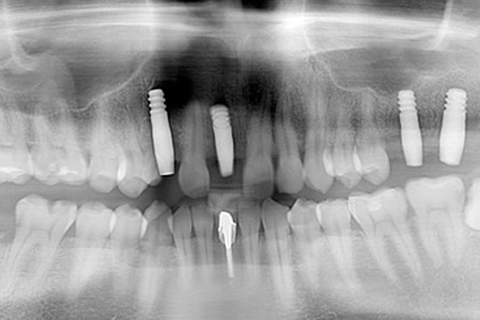

症例2

- 年齢・性別

- 57歳男性

- 治療期間

- 3ヶ月

- 抜歯

- なし

- 治療費

- 165万円

- 備考

- 左上5.6.7 及び左下6.7欠損

- 治療内容

- 左上5.6.7と左下6.7欠損部にインプラント埋入

- 施術の副作用(リスク)

- オペによる知覚障害。インプラントによる歯肉炎。インプラント脱落。